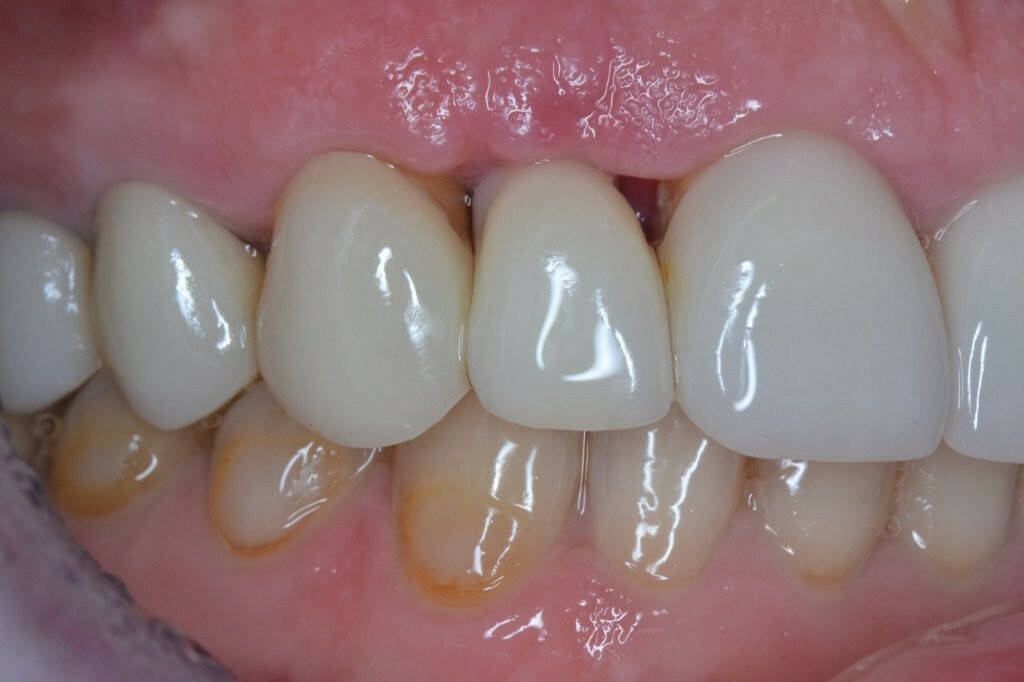

Dem Patienten wurde geraten, die OXYSAFE-Mundspülung einen weiteren Monat lang zu verwenden. Eine weitere Nachuntersuchung nach sechs Monaten zeigte eine ausgezeichnete Heilung des Weich- und Hartgewebes sowie eine schöne Regeneration der angrenzenden Papillen.